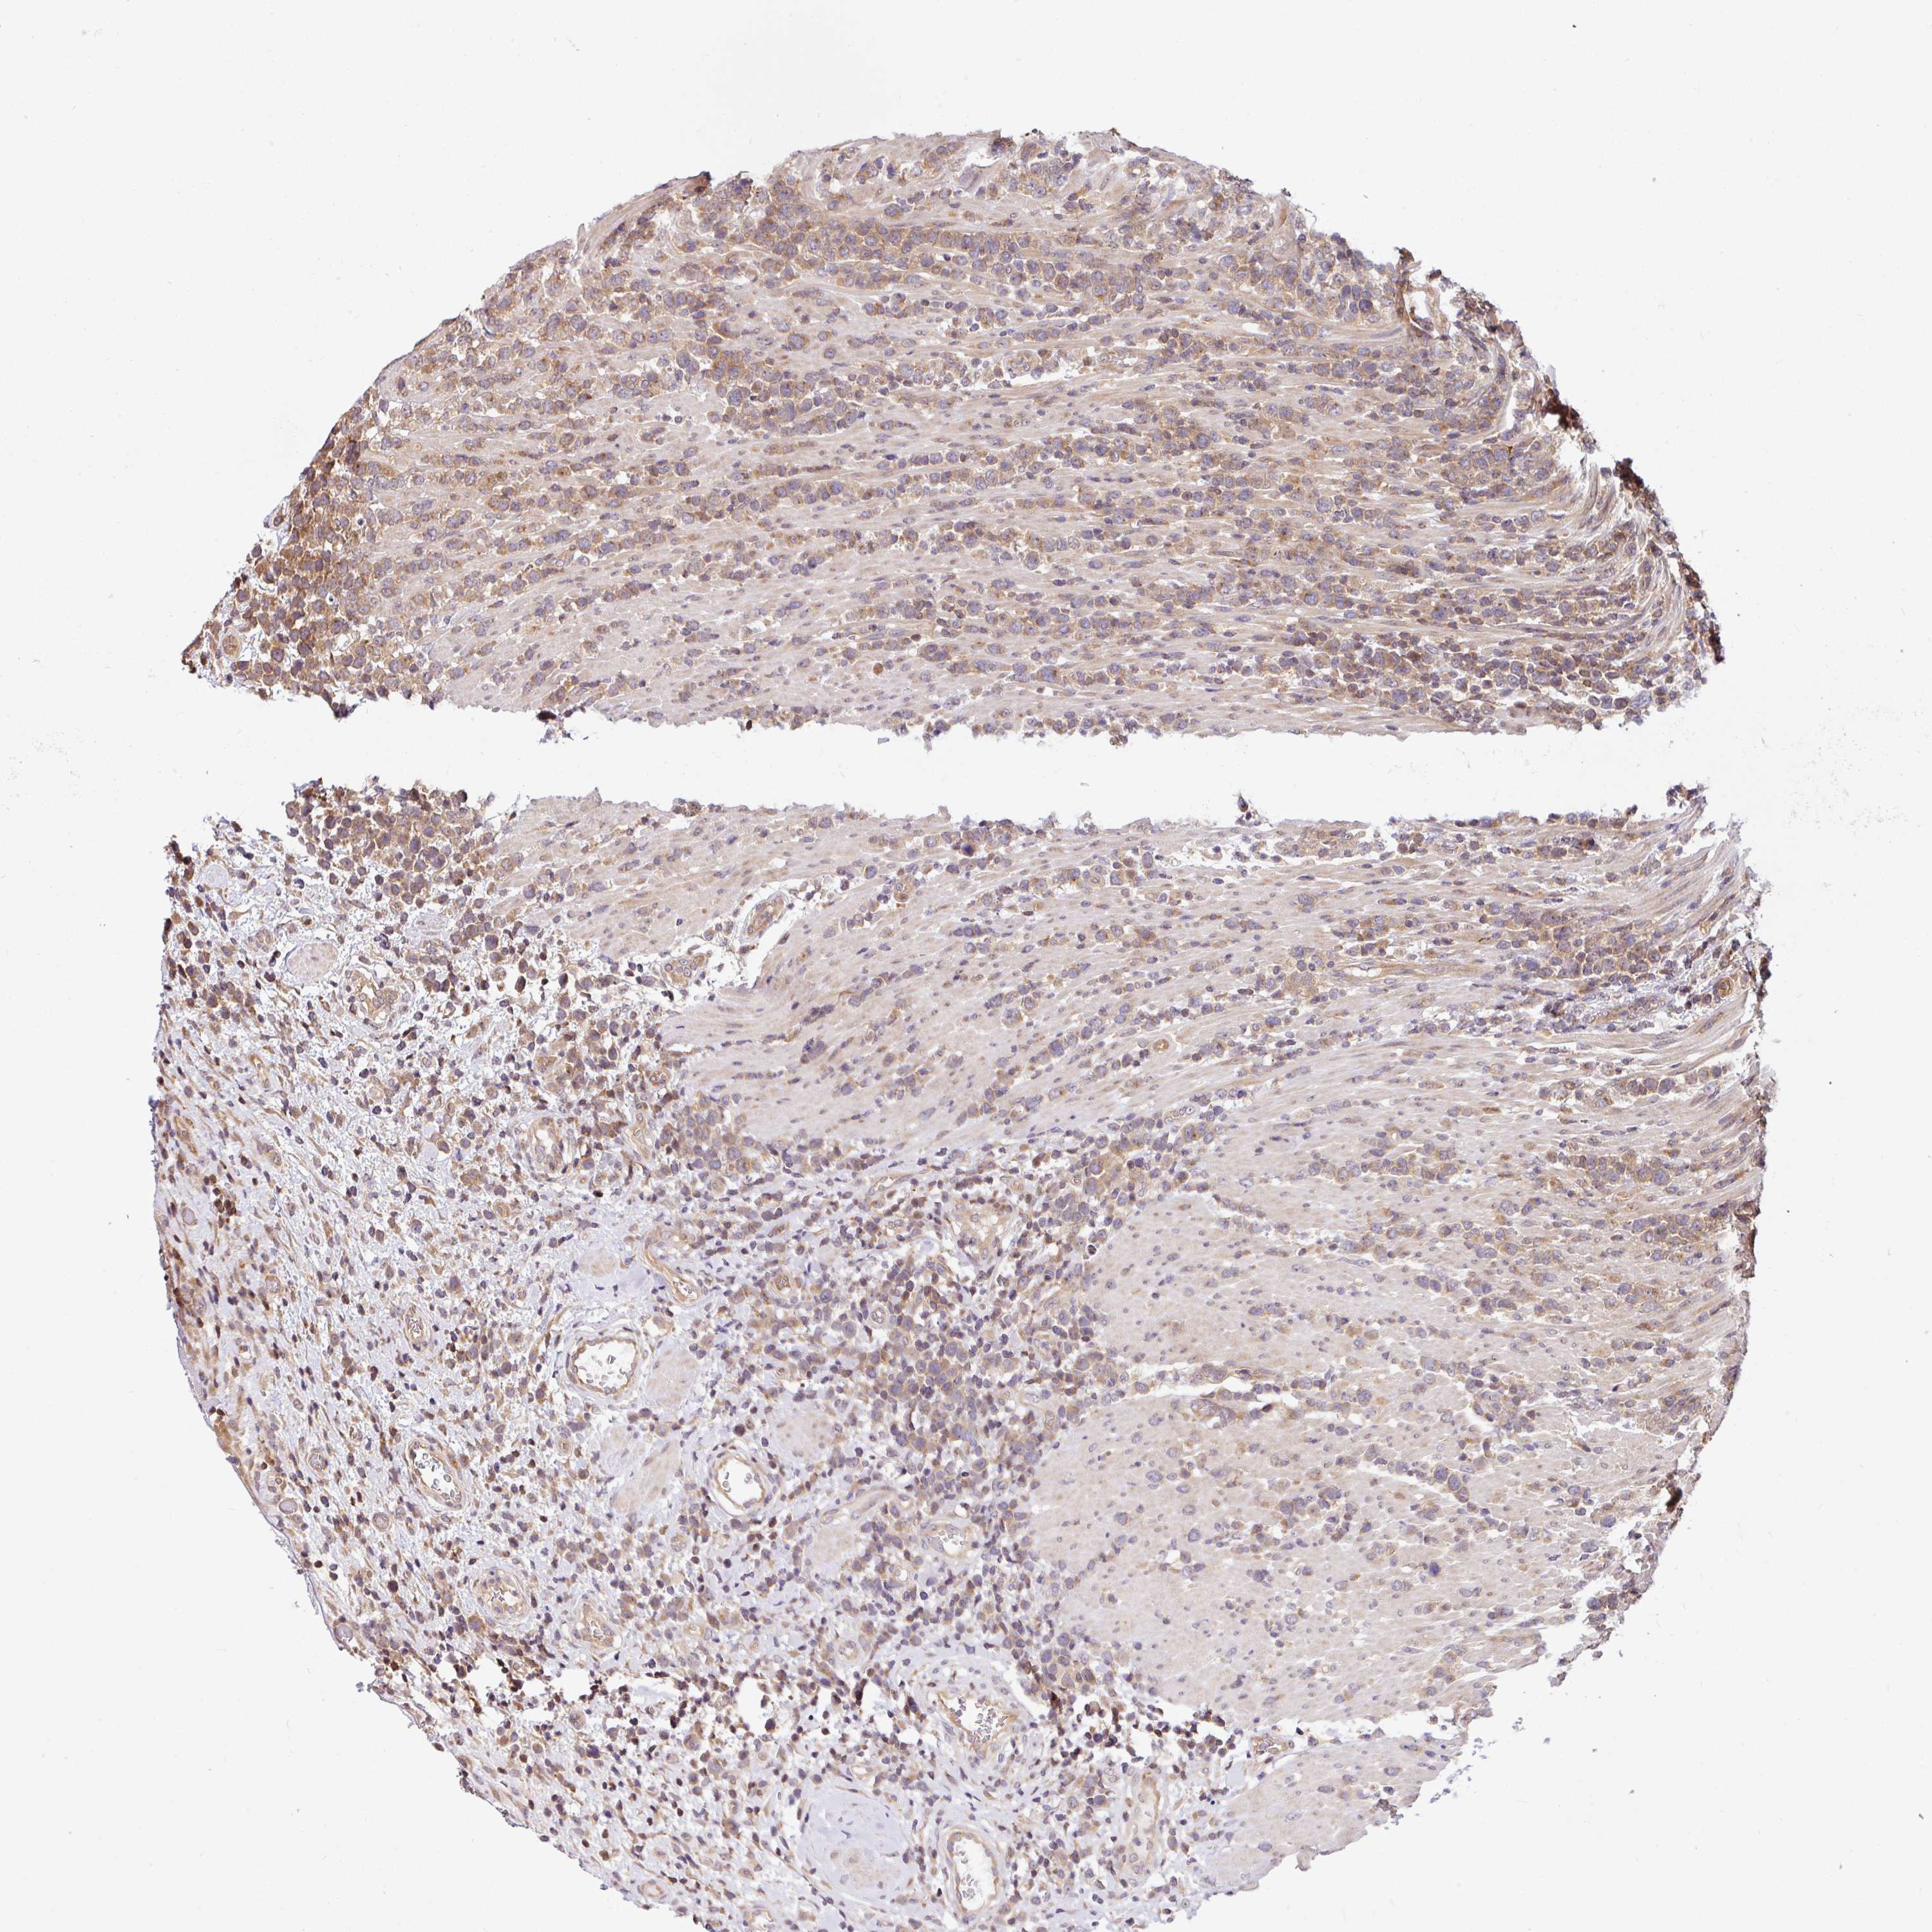

LYMPHOMA - Protein expressioni

A mouse-over function shows sample information and annotation data. Click on an image to view it in a full screen mode. Samples can be filtered based on level of antibody staining by selecting one or several of the following categories: high, medium, low and not detected. The assay and annotation is described here.

Antibody stainingi

Antibody staining in the annotated cell types in the current human tissue is reported as not detected, low, medium, or high, based on conventional immunohistochemistry profiling in selected tissues. This score is based on the combination of the staining intensity and fraction of stained cells.

Each image is clickable and will lead to virtual microscopy that enables deeper exploration of all samples and also displays staining intensity scores, fraction scores and subcellular localization as well as patient and tissue information for each sample.

Antibody HPA049911

Antibody CAB010161

Malignant lymphoma, non-Hodgkin's type, Low grade

Malignant lymphoma, non-Hodgkin's type, High grade

Hodgkin's disease, NOS